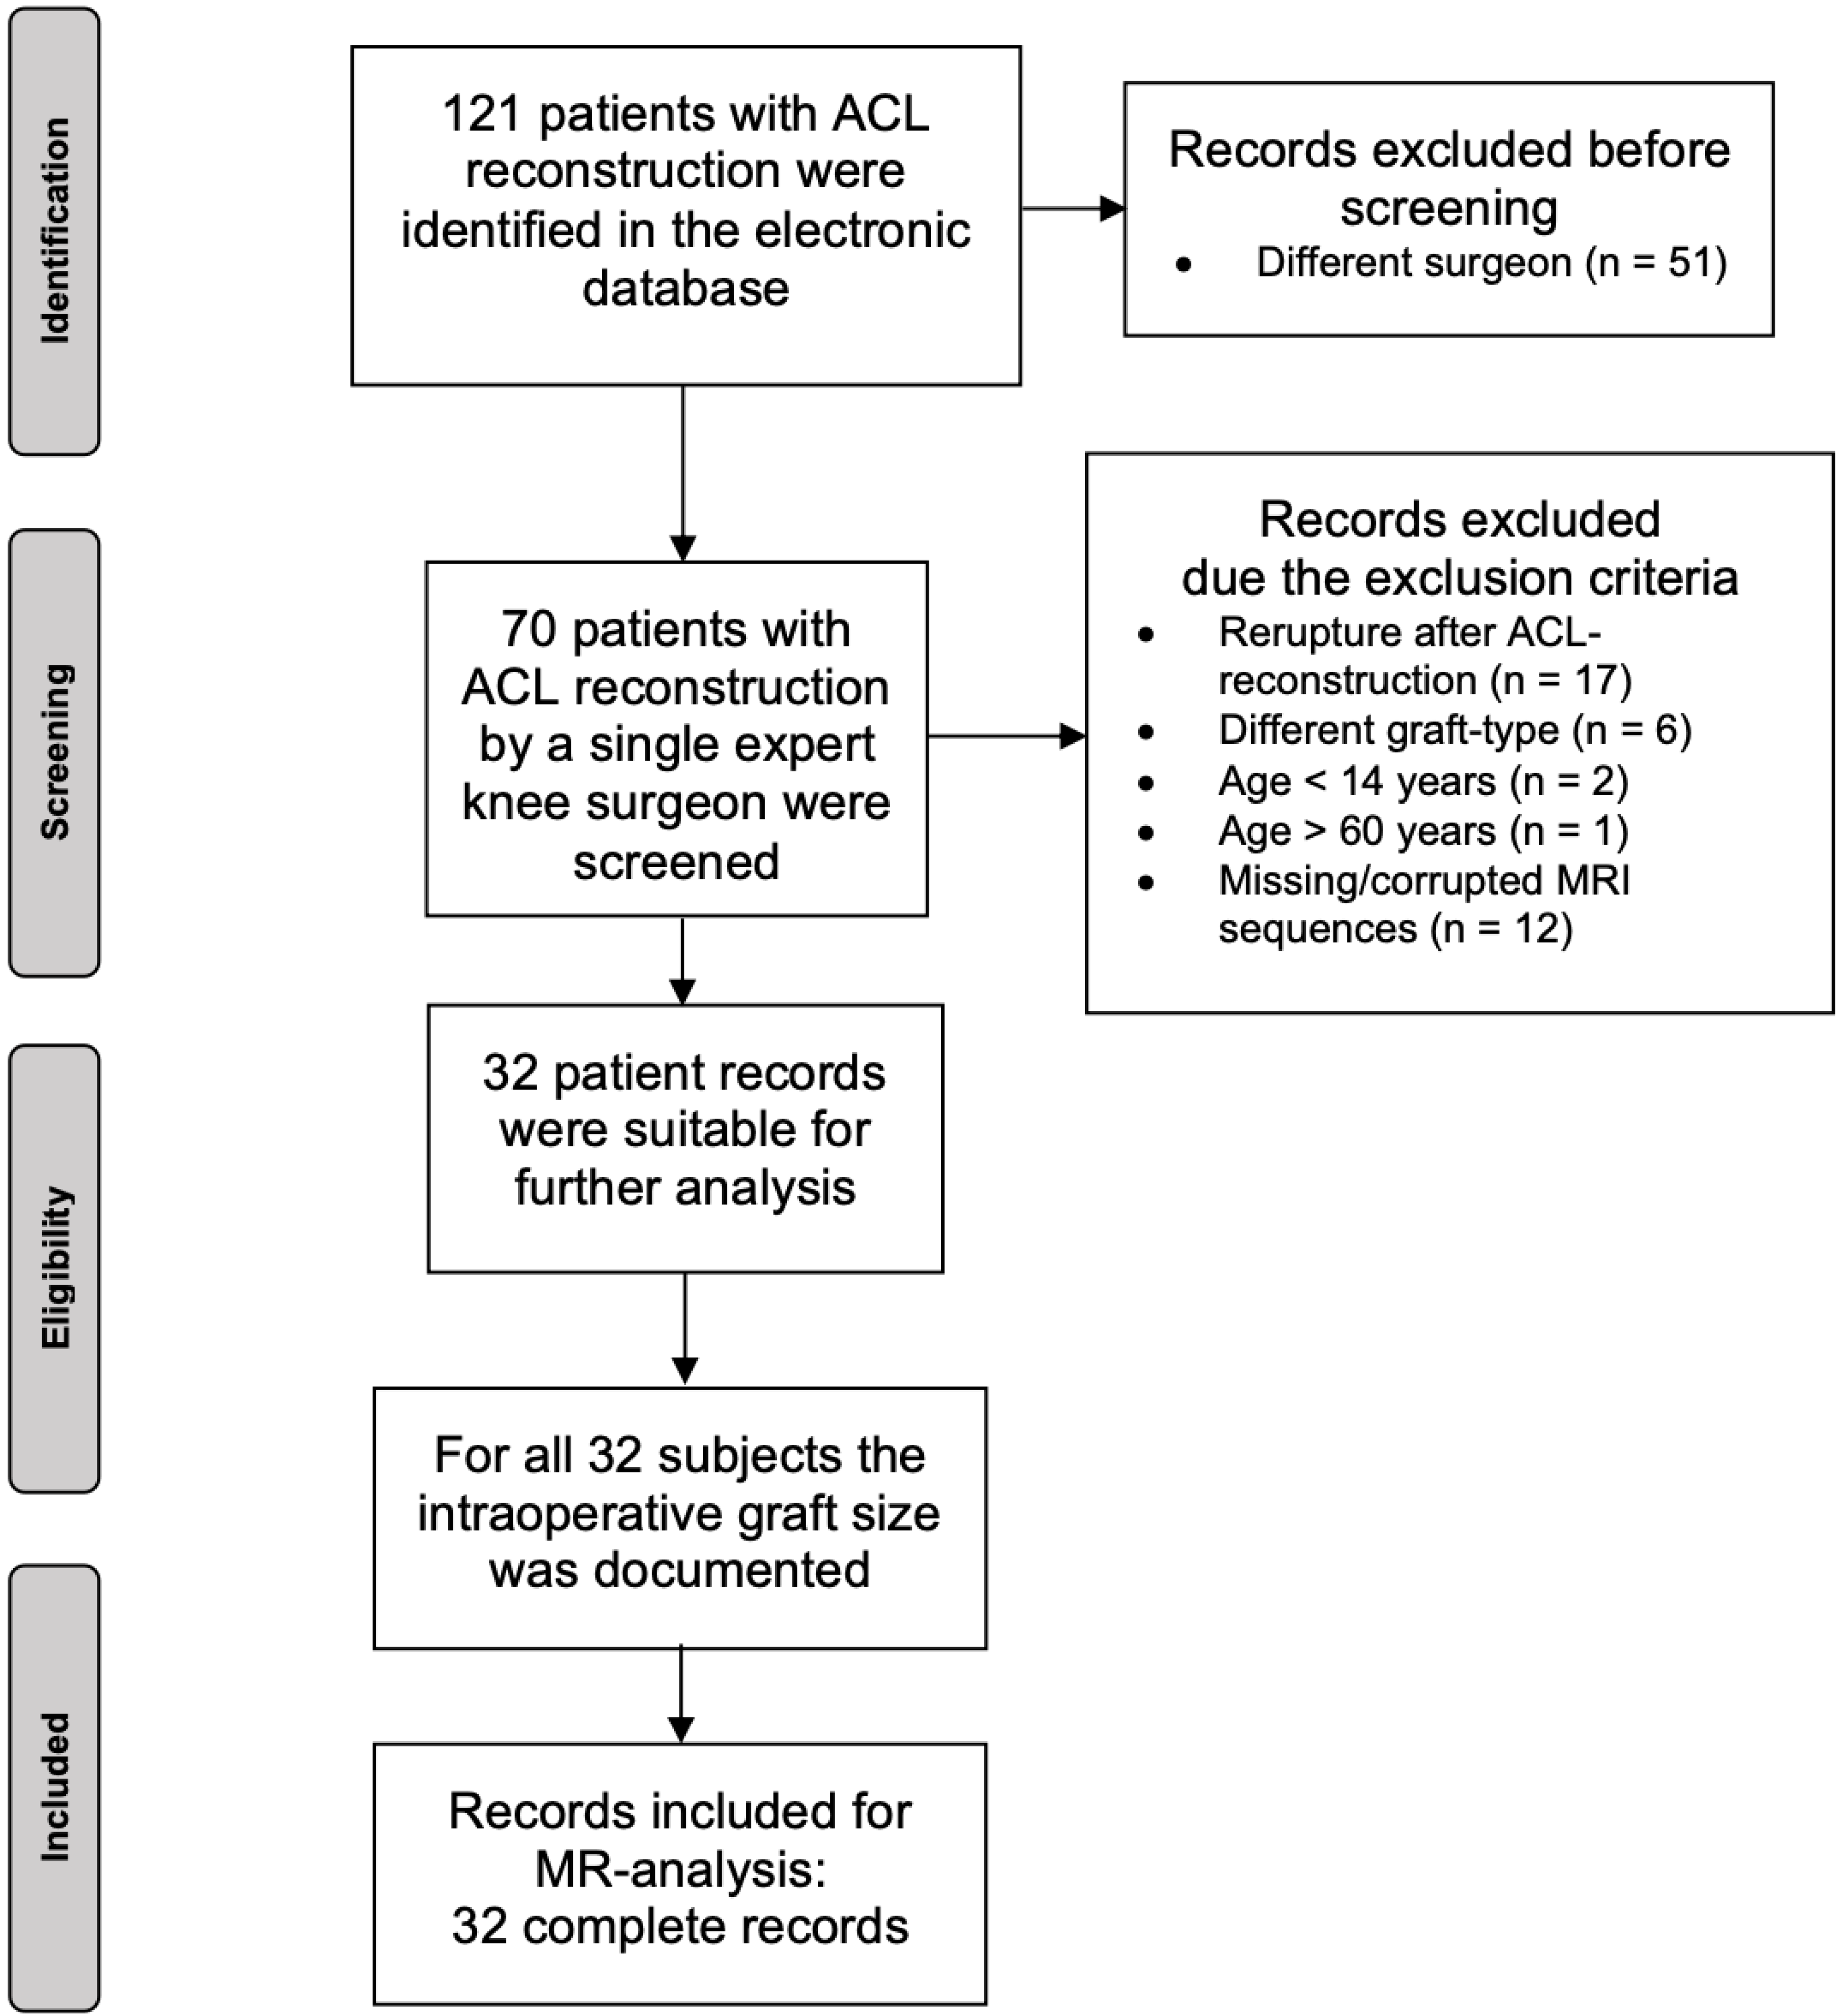

2. Materials and Methods

2.1. Patients